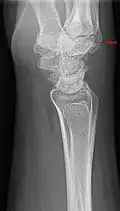

The joint between the index metacarpal and the capitate is a fibrous non-mobile joint. Some people have a gene that leads to this growth. It looks like arthritis (bone spurs on each side of the joint) on X-ray. It looks like a ganglion on the hand, but more towards the fingertips.

Carpal boss in plain X-Ray. -